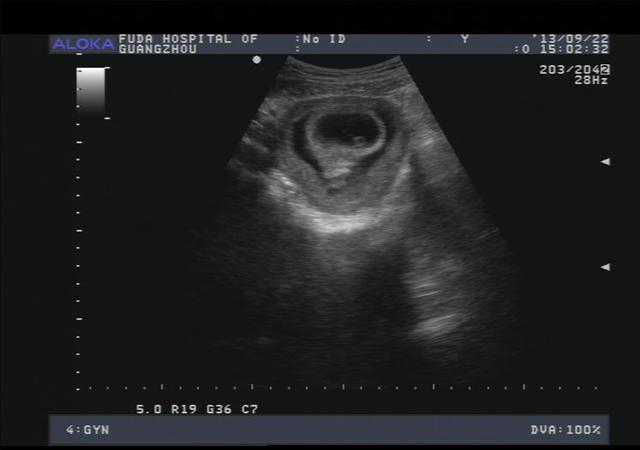

那么“翻盘”情况大多是什么原因造成的呢?答:B超或者彩超有误。

如果仔细看的话,有些医院的彩超单下方会显示“结果仅供参考”等字样,其实这也是在说结果会有误差。所以,看宝宝的性别自然也会有误差。

误差的原因①胎宝宝“走位风骚”,容易出现“女翻男”

做彩的时候,有的宝宝不配合,要么缩个团,要么双腿并的死死的,把分辨男女的最主要特征给挡住,医生护士找了半天看不到男宝宝特征,就会判断是女宝宝。

②脐带造成视觉误差,容易出现“男翻女”

妈妈的子宫空间有限,宝宝跟脐带共处一室,也算是帮宝宝解闷的一个“好室友”了。而有时候脐带所处的位置可能会比较尴尬,看彩超的时候极易让准妈妈和医生错看成男宝宝的生理特征。